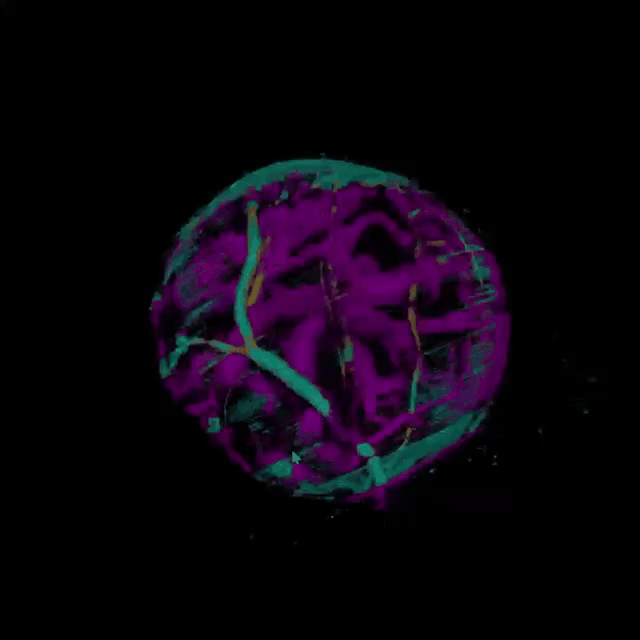

一位54岁女性患者因右眼无痛性视力丧失就诊。眼底彩照可见巨大黄白色圆形眼内占位,无明显色素沉着(A)。眼部超声提示为眼内蕈状脉络膜肿物,内部富含血流信号。磁共振成像显示眼内椭圆形肿块,T1等信号,T2高信号(C)。采用40万速超广角全域扫频OCTA北溟·鲲扫描成功获取瘤体内粗大的血流信号,3D OCTA清晰可见视网膜和肿瘤血管之间呈“双循环”模式(B),与眼底荧光血管造影结果高度一致。该患者经行右眼球摘除术,组织病理学检查可见透明细胞和黑色素细胞,确诊为无色素脉络膜黑色素瘤。

病变血管三维重建

脉络膜黑色素瘤是成年人最常见的眼内恶性肿瘤,根据瘤内黑色素含量不同,可分为黑色素型、无色素型、混合型和出血型,其中无色素型仅占15%,与典型病变有所不同,由于缺少色素, MRI的“顺磁现象”不如典型脉络膜黑色素瘤明显。该患者肿瘤瘤体巨大,但FFA早期渗漏不明显,结合其他辅助检查,可以与脉络膜血管瘤、脉络膜神经鞘瘤和转移癌相鉴别。本病例采用图湃40万速超广角全域扫频OCTA北溟·鲲,可清晰观察到肿瘤表面和瘤体内部粗大的血管血流信号,在设备上直接获得3D血管成像,更加直观立体地展示了血管生长走行特点,这在深入探索疾病特点、监测肿瘤及周围血管变化,辅助诊断和治疗方面具有重要意义。